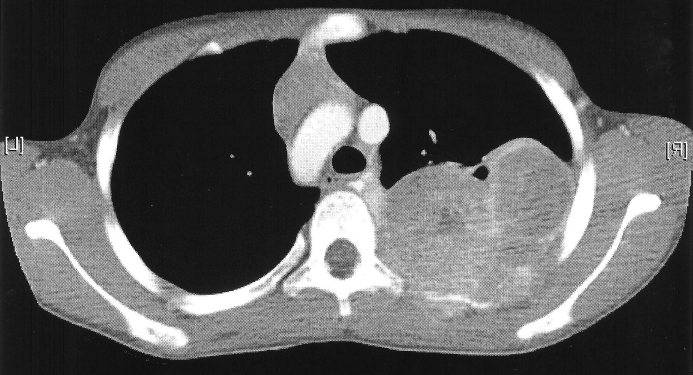

On June 25th 2007 I was diagnosed with Ewing's Sarcoma. This is a rare form of bone cancer typically only found in 10-20 year olds. This image is mirrored to reflect that the tumor was on the right side. You can click on any of the images for full images of the X-ray/Bone scan/CAT scan.

For the next 4 months I was treated with # individual rounds of chemotherapy I was brought in for surgery to remove the tumor. This surgery removed 3 of my ribs, 4-6, from spine to armpit. These were replaced with a VEPTR, Vertical, Expandable, Prosthetic, Titanium, Rib. This prosthetic is clamped onto ribs 3 and 7 spanning the vertical gap. It also has titainum wires wrapped around and inserted into the remaining rib sections to emulate the ribs. Additionally a section of Gortex was added to strengthen the chest wall. Following this surgery I had another # chemotherapy treatments bringing the total up to 14 to total rounds. On March 1st 2008 I finished my last chemo treatment.